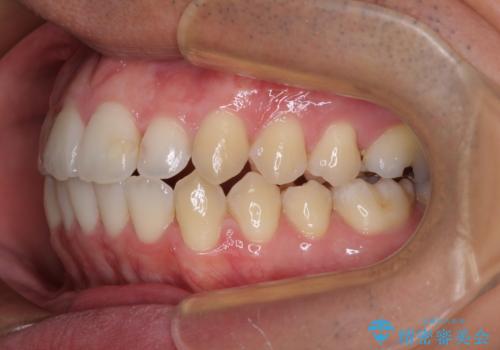

開咬とデコボコを整える インビザライン矯正治療

- 前歯の開咬と叢生を気にして来院された患者様です。

開咬の治療は、前歯を閉じるように動かすとともに、上下臼歯を圧下(骨内にめり込ませる)させることで進めて行きます。

インビザラインは臼歯の圧下を効果的に行えるため、インビザラインを用いて矯正治療を行うこととしました。また、アンカースクリューを用いて、口元の突出感の改善を図りました。